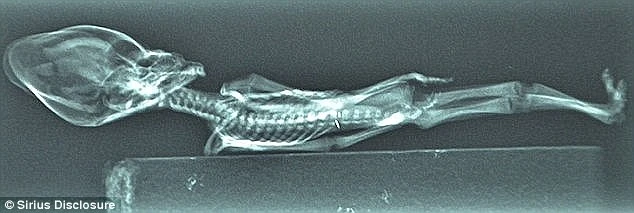

Xác ướp này được tìm thấy trên sa mạc Atacama ở Chile vào năm 2003 và sau đó thuộc sở hữu một nhà sưu tập người Tây Ban Nha. Xác ướp có tên gọi là Ata, cao chỉ 15 cm và có vẻ bề ngoài trông như những sinh vật ngoài hành tinh mà chúng ta thường tưởng tượng với bộ xương cấu tạo như người và chiếc đầu hơi bất thường.

Xác ướp chỉ dài vỏn vẹn 15 cm và như còn nguyên vẹn hoàn toàn. Ảnh: DM

Phim chụp X-quang cho thấy xác ướp tí hon có kết cấu gần như xương người, chỉ thiếu mất hai cặp xương sườn. Ảnh: DM